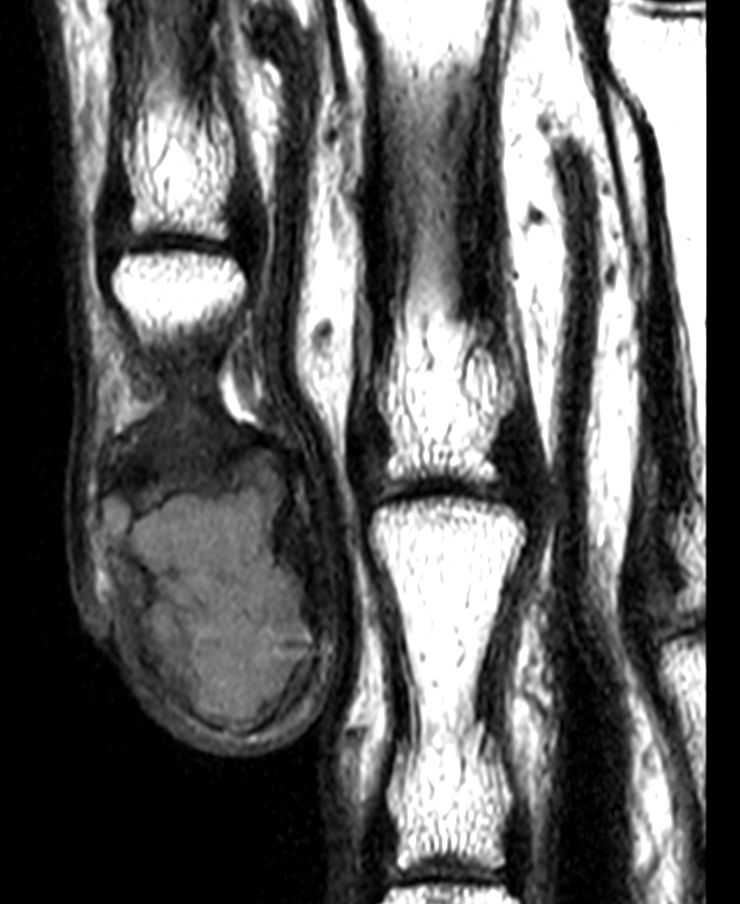

T1w TSE